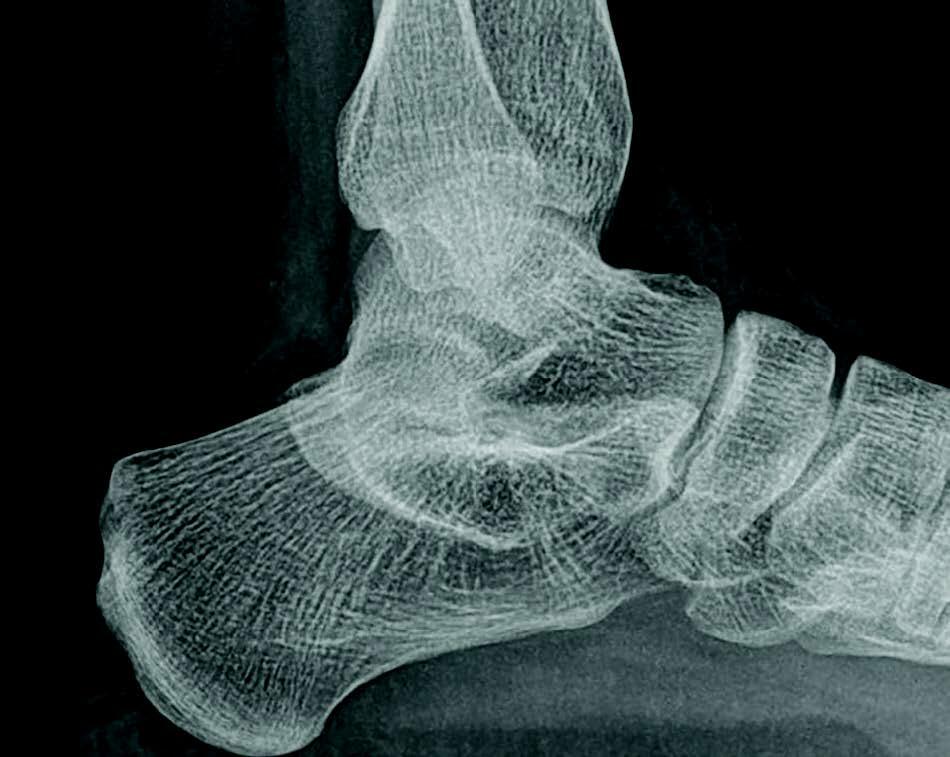

A tarsal coalition exists when there is a congenital, complete or incomplete union between two or more tarsal bones causing restricted motion or absence of motion. Tarsal coalitions remain challenging for the foot and ankle physician and surgeon. Their clinical hallmarks are primarily pain, rigid pes valgus and/or rigid pes planus deformity, and often tonic peroneal muscle spasm. Although the diagnosis of a tarsal coalition is often readily apparent upon clinical examination, diagnostic imaging is confirmatory and often aids in planning any necessary surgical intervention. Sequentially, the author always obtains radiographs of the involved foot first followed as necessary by advanced imaging with either computerized tomography (CT) or magnetic resonance imaging (MRI) scans, or in some instances of incomplete tarsal coalition, both CT and MRI.1

When conservative treatment fails, is likely to fail, or considered inappropriate, surgery is frequently indicated. Traditionally, surgical approaches for talocalcaneal coalition have been divided between resection (arthroplasty) and fusion (arthrodesis) procedures. More recently, a number of researchers attempted to provide predictable criteria for assisting in decision-making between these two diverse approaches. In 1991, this author attempted to provide a surgical classification for tarsal coalitions, including the talocalcaneal coalition.2 The criteria espoused at that time for development of a surgical treatment plan included the patient’s age (general premise: younger patients do better with resection; older patients do better with fusion), articular involvement (general premise: extraarticular coalitions do better with resection; intraarticular coalitions do better with fusion) and the extent of secondary arthritic changes (general premise: patients without arthritic changes do better with resection; patients with arthritic changes do better with fusion).2 Clearly then, the talocalcaneal coalition presents a dichotomy of options. The talocalcaneal coalition is intraarticular, and its resection by all accounts necessitates at least partial destruction of the subtalar joint. Conversely, calcaneonavicular coalitions are extraarticular and resection does not typically destroy the joint.1,2

So, do all talocalcaneal coalitions require fusion? Today, the consensus is a firm, “certainly not.” Particularly in the younger patient who has not yet reached osseous maturity, resection of a talocalcaneal coalition is an often successful consideration. Conversely, in many older patients (i.e. those who have reached developmental maturity) and/or who have secondary adaptive or arthritic changes of the surrounding joints, the surgical decision most often centers on how many joints to fuse: the subtalar joint alone; a medial double arthrodesis; or a triple arthrodesis.1 There is a “gray zone” of patients with talocalcaneal coalitions between these two extremes, where one may consider and attempt either option. Contemporary research based upon surgical treatments and clinical outcomes attempts to provide further guidance to the surgeon addressing a particular patient with a talocalcaneal coalition.

The degree of hindfoot valgus present is also a proposed possible variant in the debate between when to resect and when to fuse. Wilde and team found that more than 16 degrees of heel valgus correlated with a poor outcome after talocalcaneal coalition resection.4 Conversely, Luhmann and Schoenecker found no problems with 16 degrees of heel valgus, but did find worse outcomes with resection of talocalcaneal coalitions in patients with more than 21 degrees of heel valgus.11These investigators recommended either a medializing calcaneal osteotomy or a lateral column lengthening procedure when performing resection of a talocalcaneal coalition associated with severe hindfoot valgus.11 However, more recent research calls the negative relationship between heel valgus and the success of talocalcaneal coalition resection into question. Other investigators failed to find increased hindfoot valgus predictive of clinical outcome in their series of tarsal coalition resections.6,7